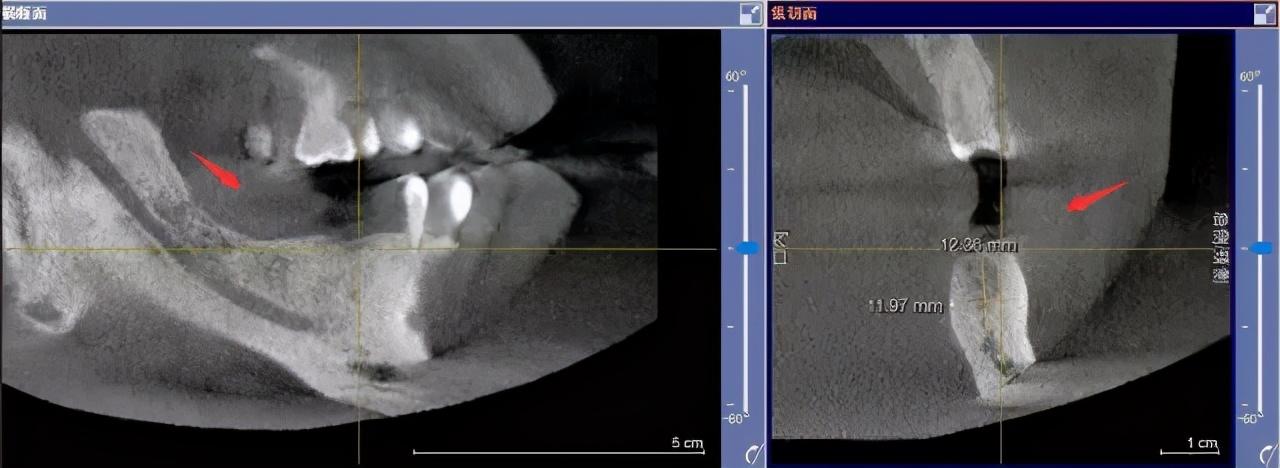

先要做一個(gè)口腔全景片、頜骨CT等

醫(yī)生根據(jù)機(jī)器成像查看口腔的具體情況,

是否有炎癥、牙槽骨的密度、吸收狀況

以及鄰牙組織、牙體組織等。

如果僅靠雙眼大致估測(cè)口內(nèi)數(shù)據(jù),是無法得到的高度、寬度的,也無法確認(rèn)骨頭吸收多少,是否需要植入骨粉。

對(duì)后期手術(shù)有一定的影響。

通過全景片可以“解剖”牙齒測(cè)量,適宜的種植角度也可確定,健康有保障。